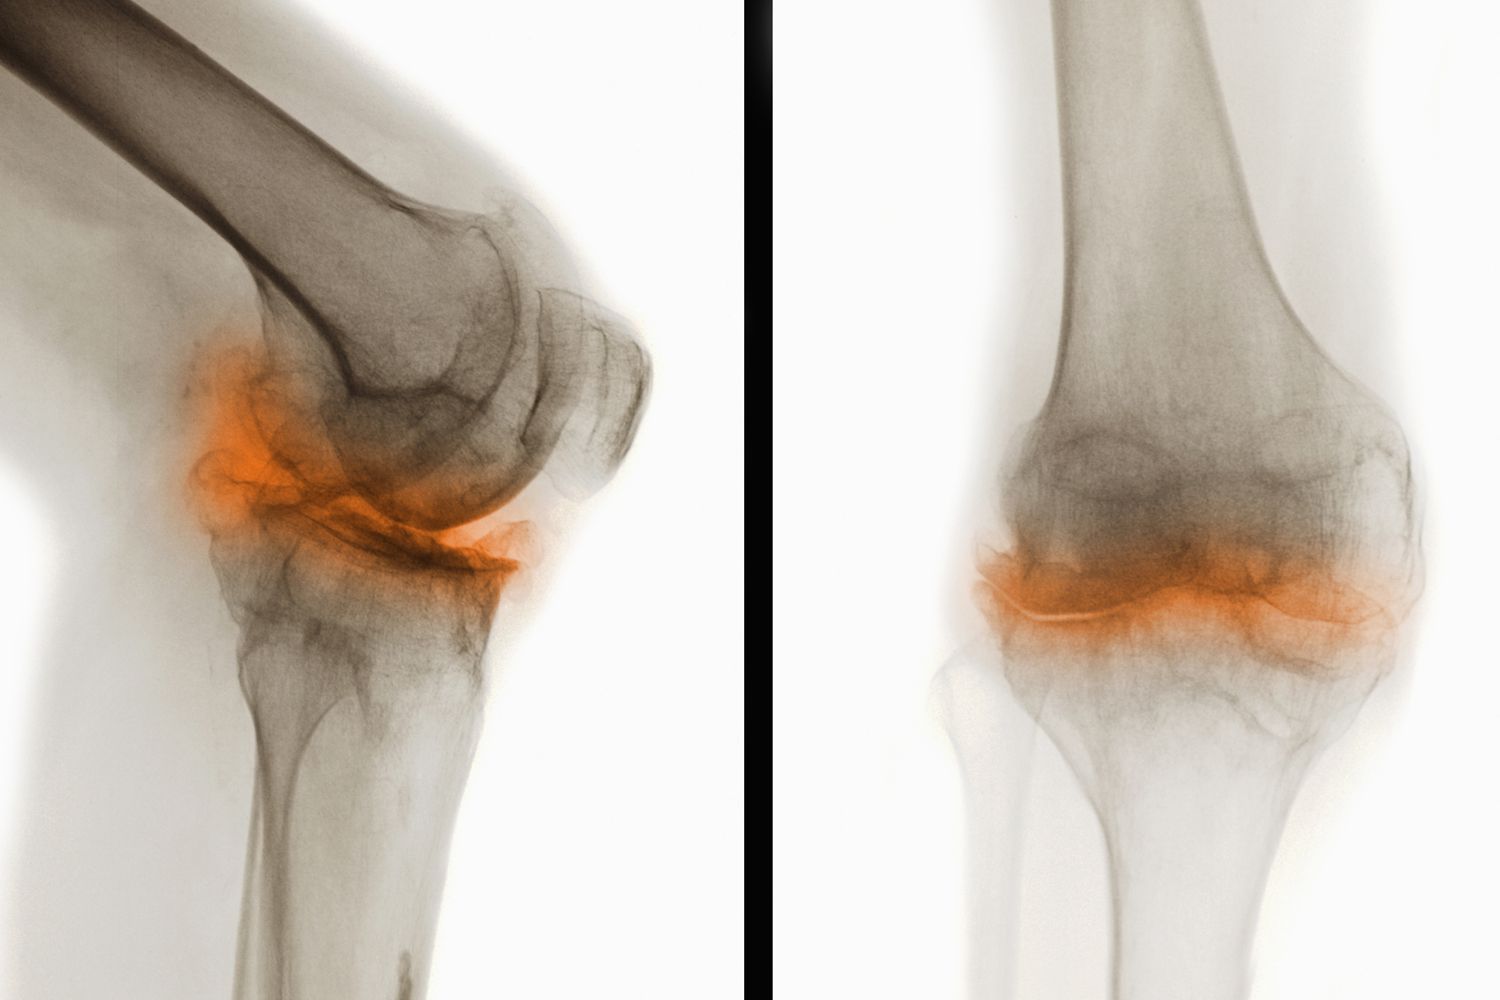

骨關(guān)節(jié)炎(Osteoarthritis,簡(jiǎn)稱(chēng)OA)是一種常見(jiàn)的慢性退行性關(guān)節(jié)疾病,主要表現(xiàn)為關(guān)節(jié)軟骨的退化和破壞,導(dǎo)致關(guān)節(jié)疼痛、僵硬和功能障礙。這種疾病通常發(fā)生在中老年人群中,尤其是負(fù)重較大的膝關(guān)節(jié)、髖關(guān)節(jié)、脊柱及遠(yuǎn)側(cè)指間關(guān)節(jié)等部位。